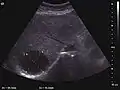

The ultrasound appearance is a well defined lesion, with very thin, almost unapparent walls, without circulatory signal at Doppler or CEUS investigation. The content is transonic suggesting fluid composition. The presence of membranes, abundant sediment or cysts inside is suggestive for parasitic, hydatid nature. Posterior from the lesion the acoustic enhancement phenomenon is seen, which strengthens the suspicion of fluid mass. They typically displace normal liver vessels but no vascular or biliary invasion occurs.

Liver cyst

Hydatid liver cyst. Diagnostic criteria are the presence of membranes and sediment inside.